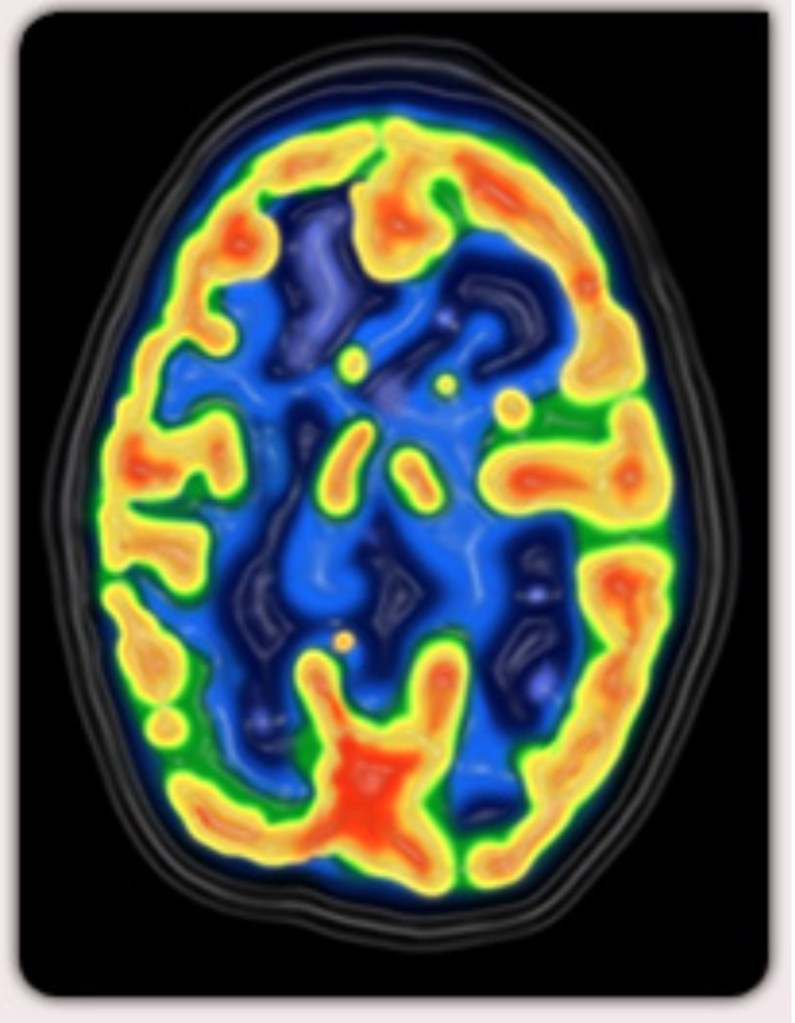

Que se passe-t-il lors de notre vieillissement ? Est-il possible d’améliorer nos capacités mnésiques ? Tous concernés par cette problématique. Scientifiques, chercheurs sont au chevet et tentent de répondre à ces questions. Cette question anime les débats surtout que la maladie d’Alzheimer, maladie neuro dégénérative du tissu cérébral est incurable à ce jour. Nos ainés sont de plus en plus victimes de cette perte progressive et irréversible des fonctions mentales et notamment de la mémoire.

L’hypnose est reconnue, et ce faisant suite aux récentes découvertes scientifiques sur le fonctionnement du cerveau.

A condition d’être patients, l’inconscient accomplira à notre insu et fera remonter ce qui est enfoui profondément en nous, puis gommera toutes ces imperfections accumulées au cours de notre existence. Les neurosciences avancent de plus en plus dans les techniques mises en œuvre par l’hypnose.